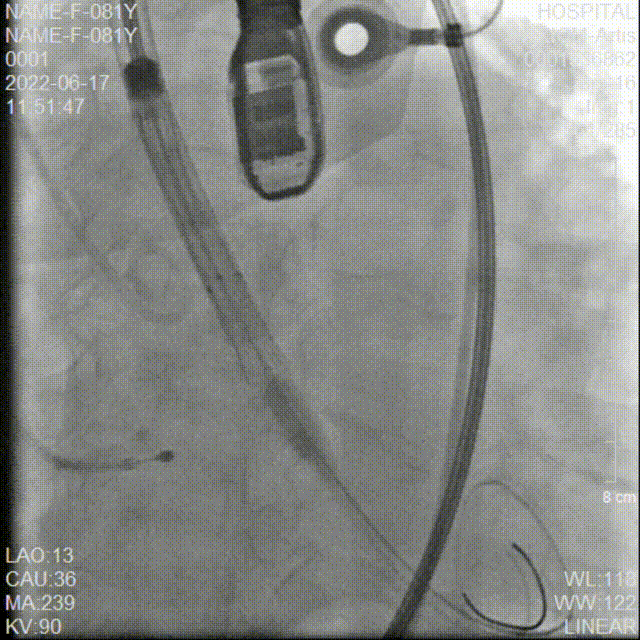

20mm球囊预扩